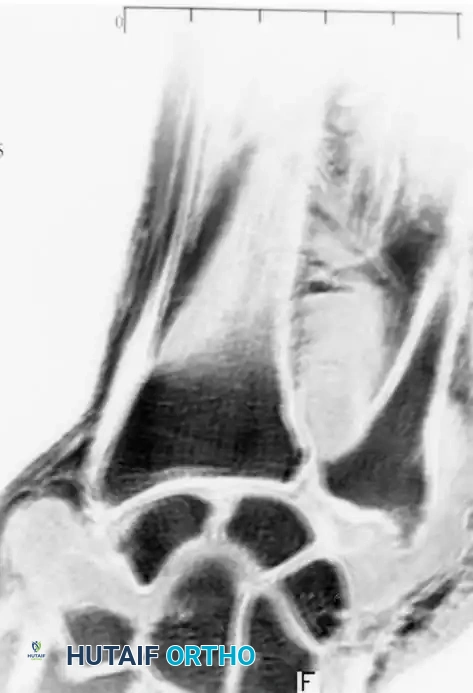

Fig. 74-19 C, MRI detailing the extent of cartilaginous loose bodies within the joint capsule.